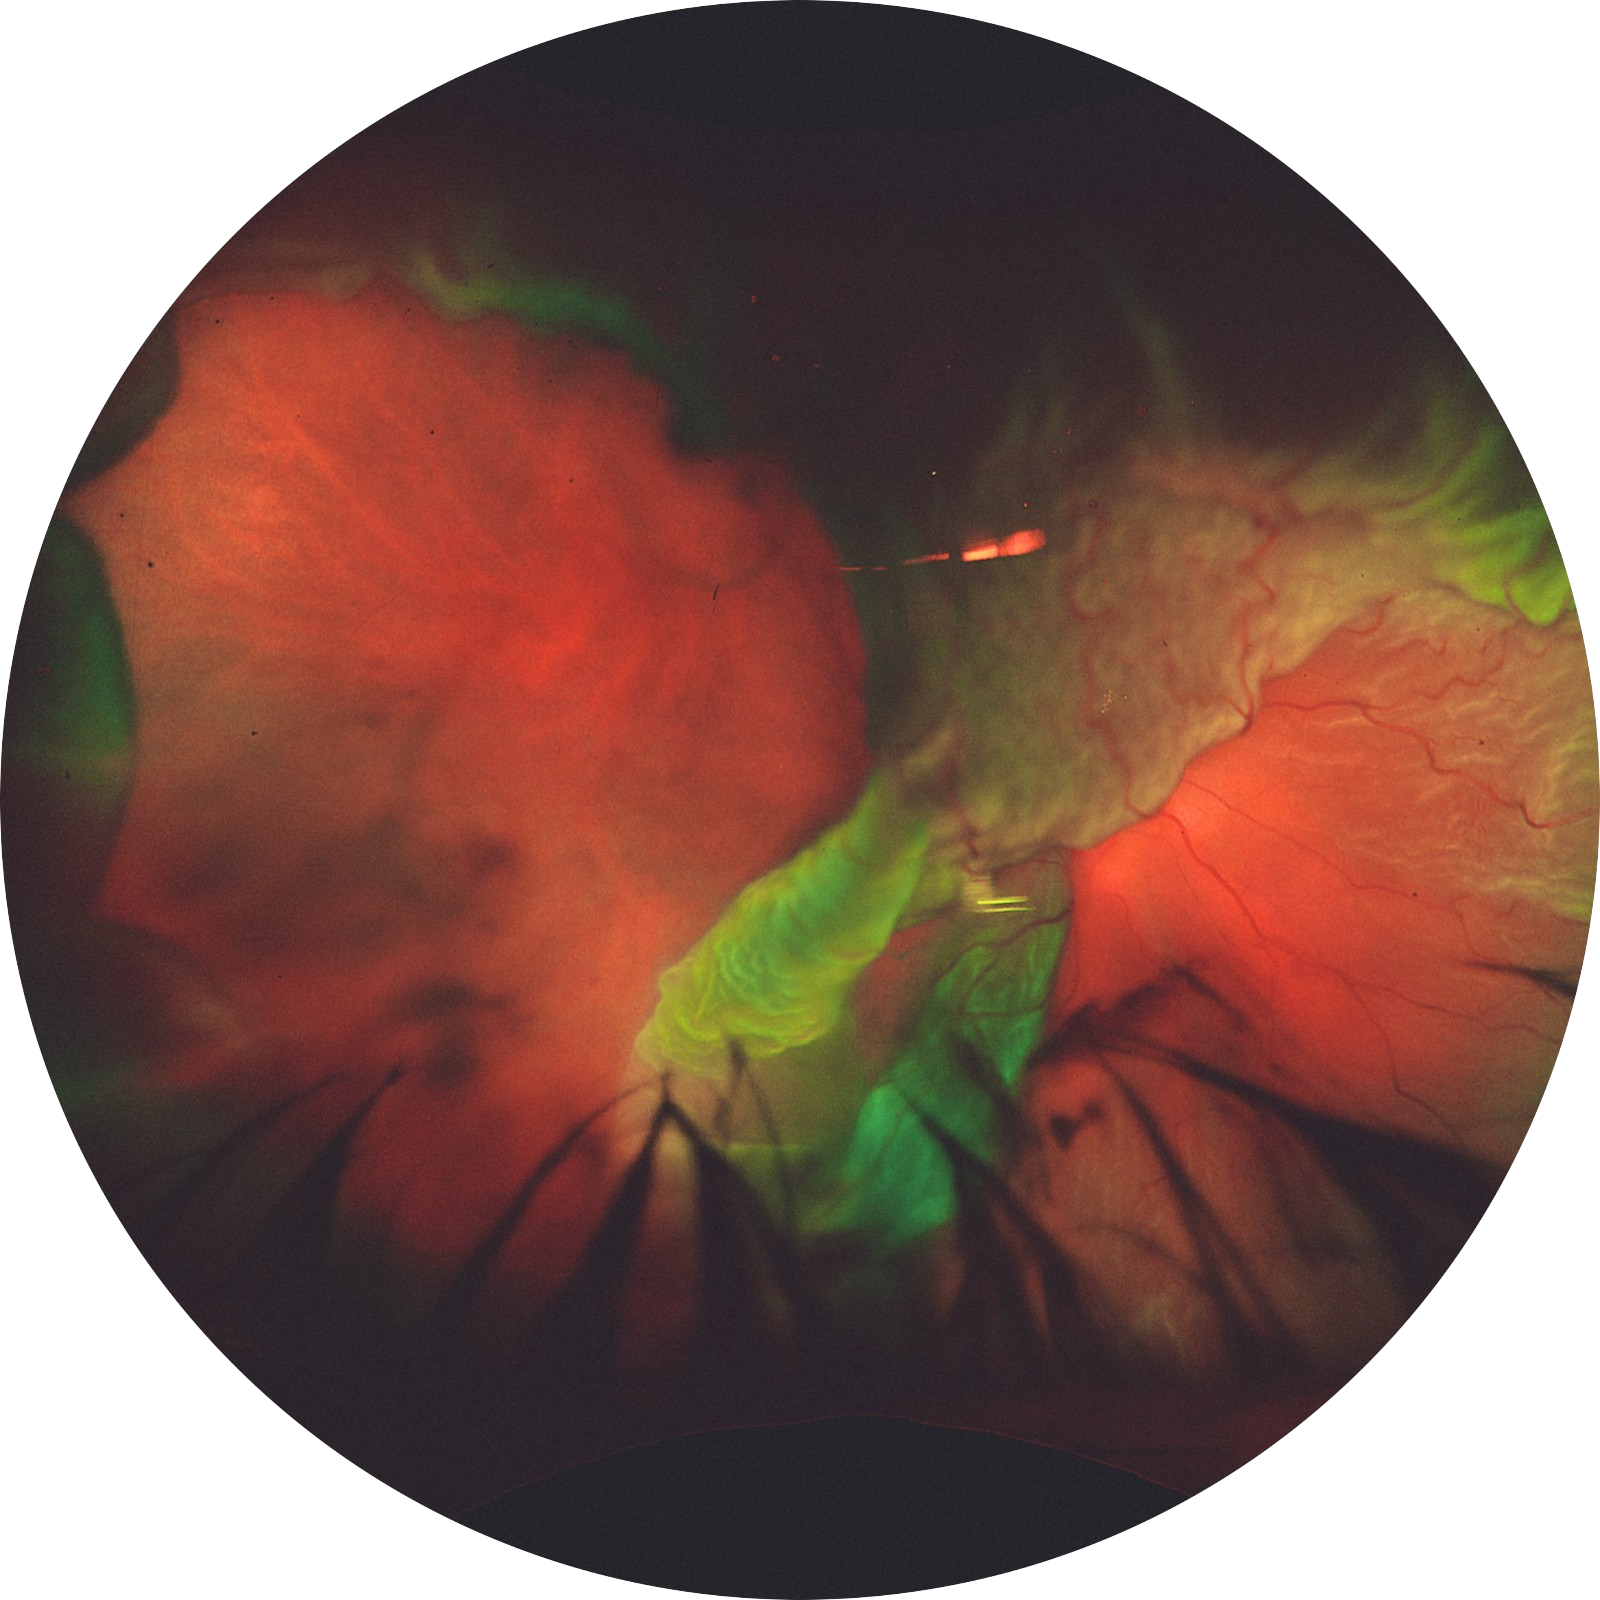

RETINAL TORNADO: THE FURY OF GIANT RETINAL TEAR. Optos ultrawield field retinal imaging camera image

Author: Dr. ABHISHEK G NAIR